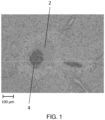

• the self-assembled peptides have a fibrous microstructure with small pores as revealed by electron microscopy.

• the self-assembling peptides of the present disclosure may have a nanofiber diameter in a range of about 10 nm to about 20 nm and an average pore size is in a range of about 5 nm to about 200 nm.